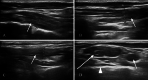

Thoracic outlet syndrome (TOS) is a rare neurovascular disorder generally caused by the presence of a cervical rib or hypertrophic scalene anterior muscle that can compress the brachial plexus and/or subclavian vessels. In the vascular form, the symptoms are caused by the compression of the artery and/or the subclavian vein. In the first case, the compression is caused by the cervical rib and leads to hypo-perfusion with cooling and cyanosis of the upper limb, while in the second case, the compression is caused by the anterior scalene muscle and leads to congestion, cyanosis, swelling and pain in the higher limb. In this paper, we describe a case with the simultaneous presence of a bilateral cervical rib and bilateral hypertrophy of the anterior scalene muscle. TOS diagnosis is based on neurological, clinical and instrumental tests, such as chest radiography and color Doppler ultrasonography. The treatment of these patients can be surgical or conservative.